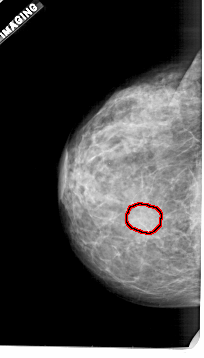

FILE: A_1921_1.LEFT_MLO.OVERLAY TOTAL_ABNORMALITIES 1 ABNORMALITY 1 LESION_TYPE MASS SHAPE OVAL MARGINS OBSCURED ASSESSMENT 3 SUBTLETY 2 PATHOLOGY BENIGN TOTAL_OUTLINES 1 BOUNDARY |

FILE: A_1921_1.LEFT_CC.OVERLAY TOTAL_ABNORMALITIES 1 ABNORMALITY 1 LESION_TYPE MASS SHAPE OVAL MARGINS OBSCURED ASSESSMENT 3 SUBTLETY 2 PATHOLOGY BENIGN TOTAL_OUTLINES 1 BOUNDARY |